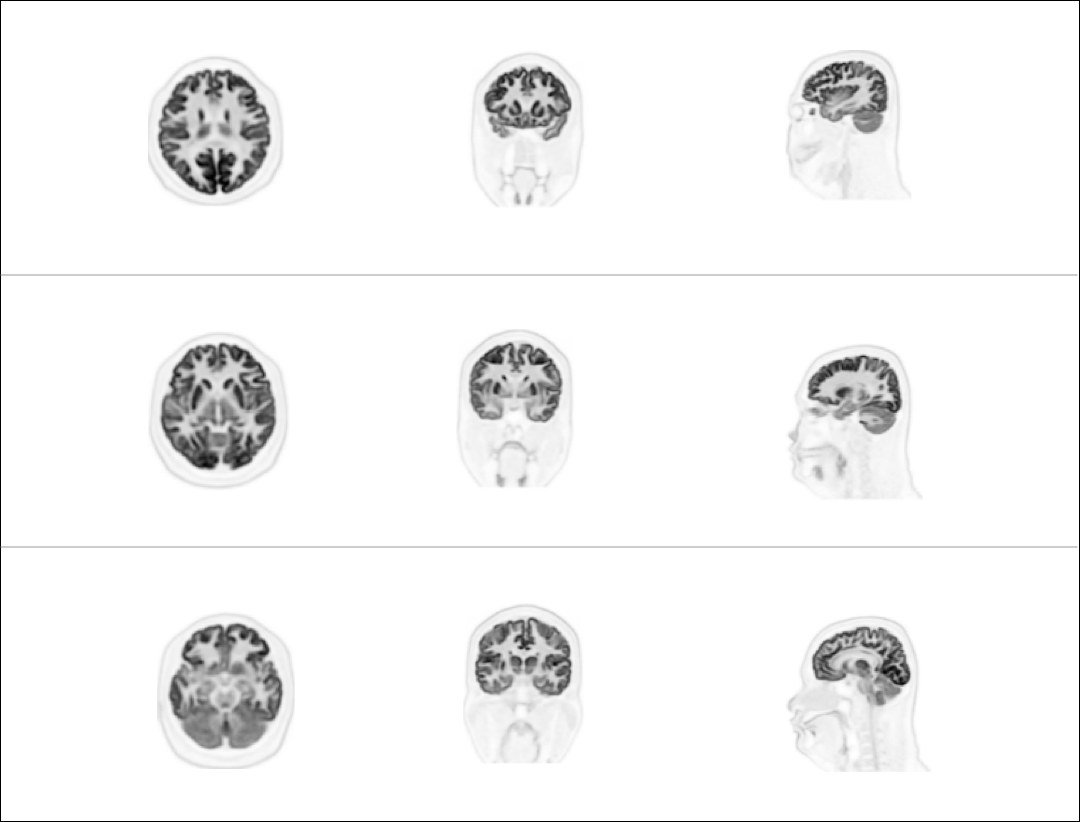

高清脑部显像